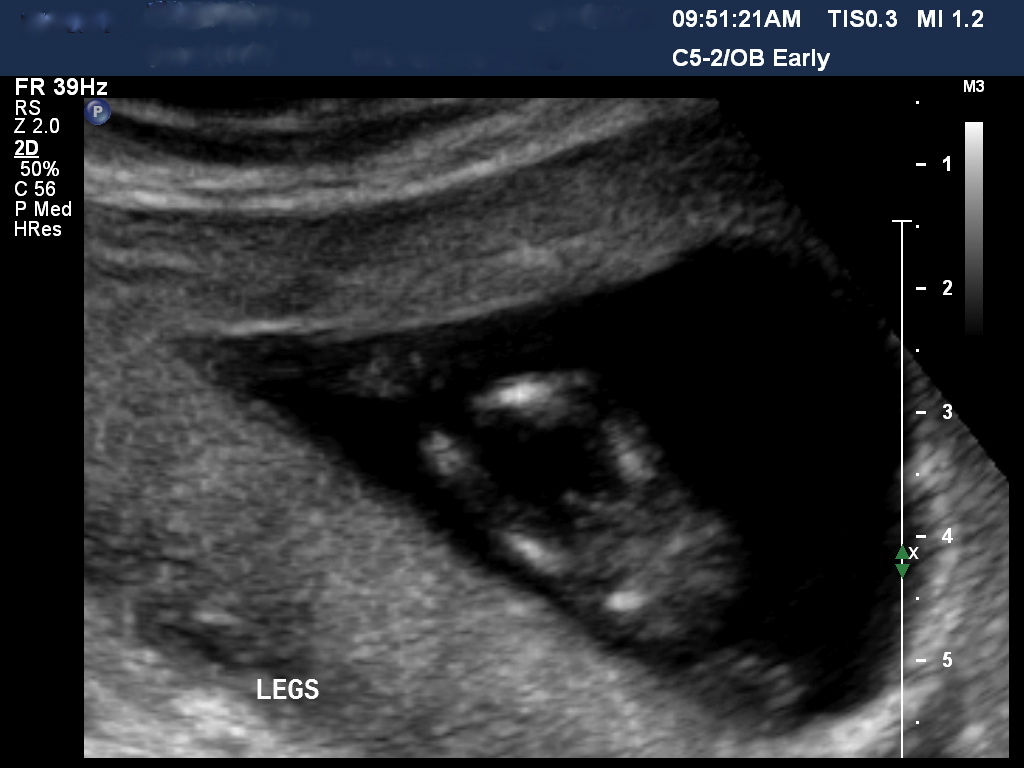

Hi All trying to pick the gender but need help please??? Boy or girl 12.5 week u/s Attachment 6766Attachment 6767

I'd got with boy. The potty shot looks boyish and the angle of the nub is upwards and not flat.

Yes i think the skull is boyish too, see how the forehead is kind of flat looking, where girly skulls are really rounded.

Yes, boy skull and boy nub!

Just had my 20 week scan and is confirmed 100% Boy to all those who took a guess you are correct!